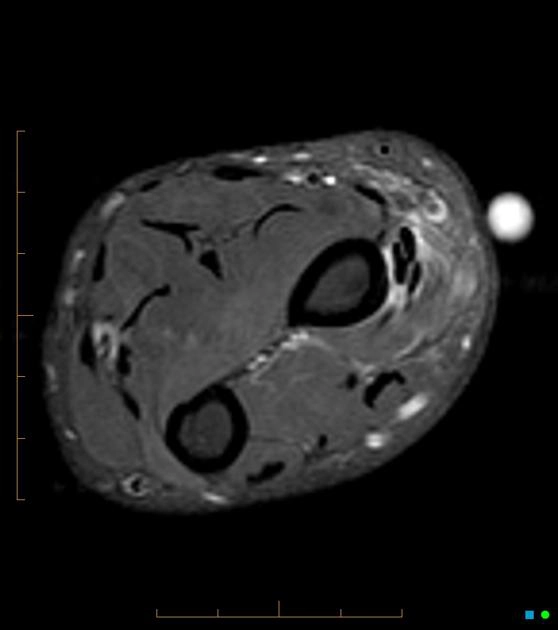

Tổn thương phức hợp sụn sợi tam giác (Triangular fibrocartilage complex - TFCC injury)

16/03/2026